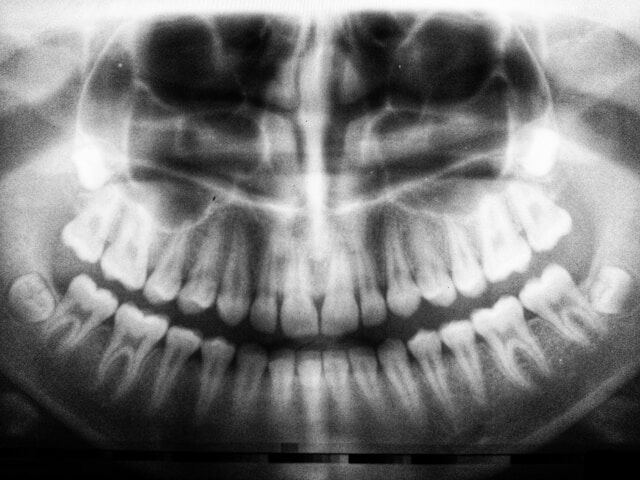

leer mas Dentro de la rama de la odontología se utilizan diferentes técnicas para diagnosticar problemas dentales que no son detectables a simple vista, y uno de los más comunes es la OPG u ortopantomografía. Saber qué es una ortopantomografía dental y para qué sirve te permitirá comprender mejor de qué se trata y cuándo es necesaria.